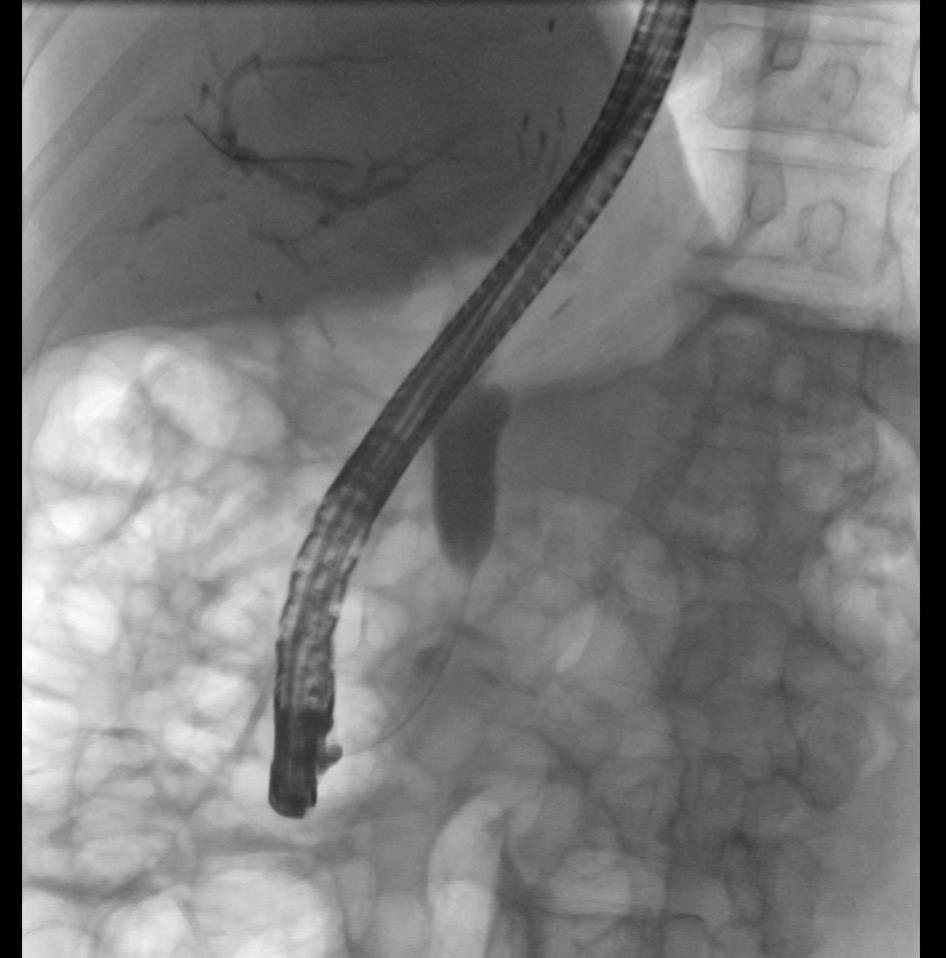

胆管癌梗阻性黄疸ERCP术中N多次想放弃。想想患者还是坚持了,成功那一刻的喜悦,吃再多的射线都是值得的